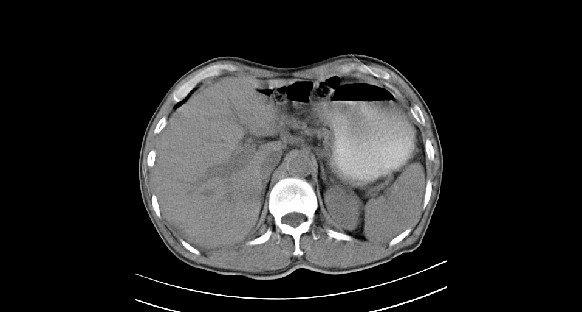

男性,70岁,体检b超发现左肾占位,请各位战友发表一下观点

左肾有两个病灶,且较大的病灶内可见点状钙化灶,增强扫描边缘也是呈渐进性强化,中央部分未见明显强化